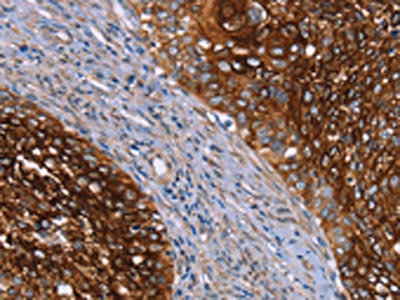

• The image on the left is immunohistochemistry of paraffin-embedded Human cervical cancer tissue using CSB-PA257925(CRH Antibody) at dilution 1/20, on the right is treated with synthetic peptide. (Original magnification: ×200)

• The image on the left is immunohistochemistry of paraffin-embedded Human thyroid cancer tissue using CSB-PA257925(CRH Antibody) at dilution 1/20, on the right is treated with synthetic peptide. (Original magnification: ×200)